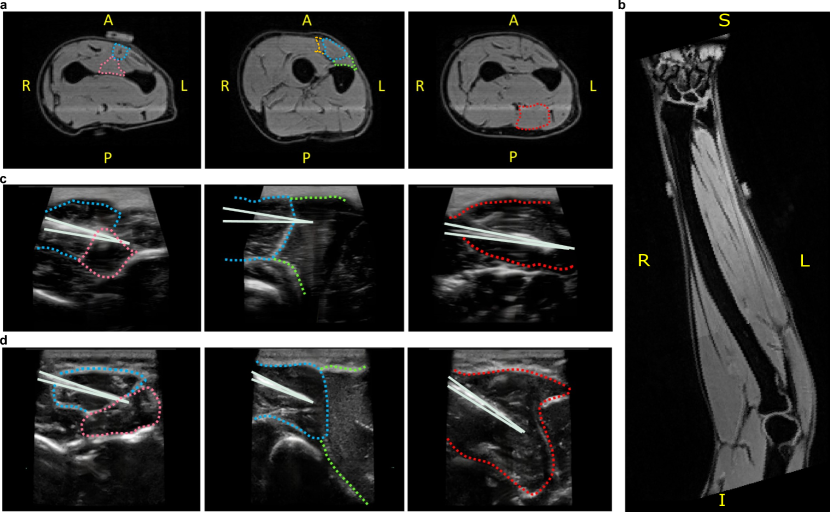

The recording of multiple high-density intramuscular data arrays represents one of the key innovations of this study. HD-iEMG enables recordings from a significantly larger number of sites compared to traditional needle or wire electrode arrays [14]. Furthermore, HD-iEMG signals exhibit greater spatial and temporal sparsity than HD-sEMG, allowing for more precise analysis of motor neuron activity [13]. In this study, three HD-iEMG electrodes were inserted in the forearm muscles of two healthy participants, with one electrode placed in each of the most relevant extrinsic muscles for finger flexion and extension. Interfacing with motor units that control hand function poses inherent challenges due to the precise targeting required for intramuscular electrode placement in the primary muscles responsible for dexterous control. Optimal electrode placement sites were determined via a magnetic resonance imaging (MRI)- and ultrasound-based anatomical assessment of the forearm. MRI was employed to gain a detailed understanding of the forearm muscle anatomy and to guide the insertion point and angle of the electrodes. Specific forearm points were tracked using MRI markers across scans, allowing precise localization of marker positions and detailed insights into forearm structure (Fig. 2 a). Each electrode array, comprising 40 platinum electrodes (140 μm×\mu m\times 40 μm𝜇𝑚\mu m) linearly distributed over 2 cm with 0.5 mm inter-electrode (IED) spacing [13], targeted muscles involved in finger movements. The insertion of each array was facilitated by a 25-gauge hypodermic needle, which was attached to the electrode with a guiding filament. Once the electrode was positioned, the filament was cut, allowing the needle to be removed while the electrode remained securely in the muscle.

MRI provides a comprehensive anatomical view of the forearm, but practical constraints limit its use during needle insertions. Once the electrode insertion points and general positioning were identified using MRI, precise muscle targeting during the actual insertion became essential to avoid veins, arteries, and nerves. This necessitated real-time imaging guidance to ensure accurate and safe insertion. A portable ultrasound device (Butterfly iQ+) was used to precisely visualise electrode paths to target muscles in real-time (Fig. 2 c and d, for Subject 1 (S1) and Subject 2 (S2), respectively). Post-insertion, subjects performed maximal muscle contractions (MVC) as reference for submaximal tasks. This procedure also confirmed secure electrode placement and minimised the risk of displacement.

While electrode placement followed the above rigorous procedure, some errors in the exact target placements occurred. For example, the limited field of view of the ultrasound probe impeded the full tracking of the micro-electrode array targeting the EDM for both subjects (panels c, d, second column). The extension of the insertion to the boundary of the Extensor Carpi Radialis Brevis (ECRB) suggests that the electrode might not have fully targeted the EDM, potentially failing to record specific information related to the little finger tasks. Moreover, although the EPL was targeted in both subjects (panels c, d, first column), the number of channels within the muscle was relatively small (panels c, d first column). This potentially impacted the amount of information recorded from the EPL during these tasks. The micro-electrode arrays were acutely implanted in the target muscles with percutaneous wires.

Figure 2: MRI and ultrasound images of the forearm with the boundaries of the relevant muscles highlighted in color (EPL: pink, EDC: blue, EDM: orange, ECRB: green, FDS: red). a MRI scans of the forearm of one subject with highlighted boundaries of the targeted muscles. The first MRI image includes a marker for precise positioning within the forearm’s anatomical structure. b Detailed MRI view of the forearm. c, d Ultrasound image during the micro-electrode array insertion for subject S1 (c) and subject S2 (d). The guiding needle is highlighted in white.